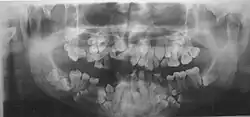

Panoramic view of the jaws showing multiple unerupted supernumerary teeth mimicking premolar, missing gonial angles and underdeveloped maxillary sinuses in cleidocranial dysplasia. -